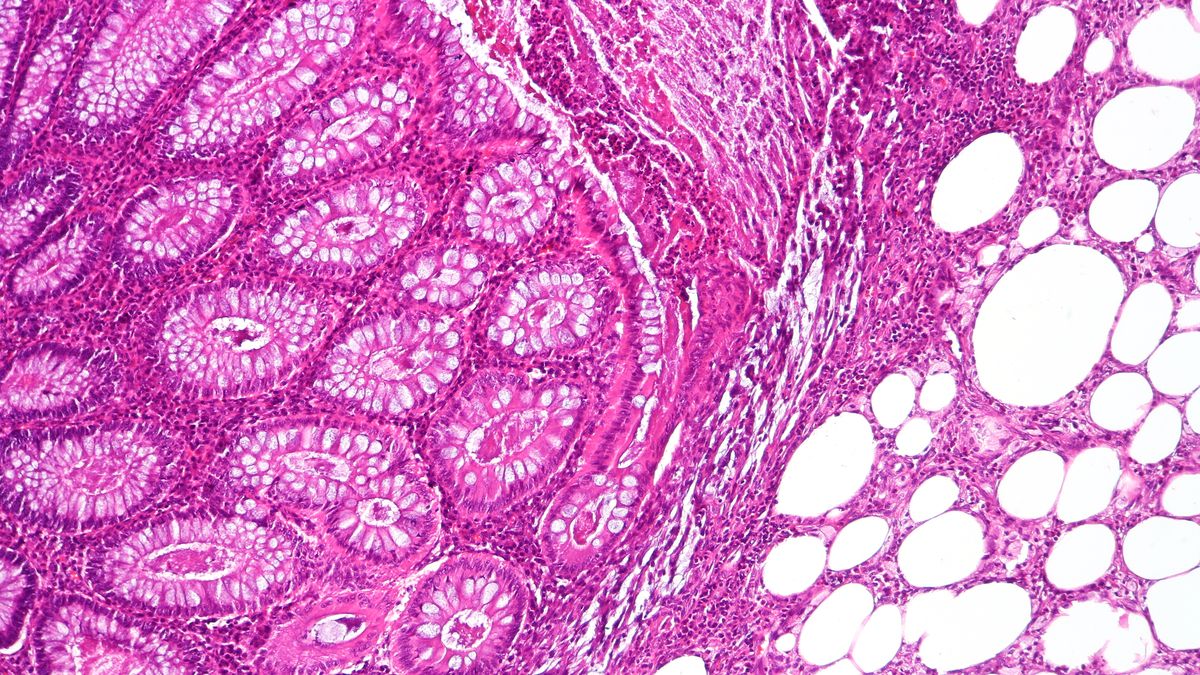

Según explica el sitio especializado en medicina Mayo Clinic, los divertículos son bolsas abultadas y pequeñas que se pueden formar en el revestimiento del sistema digestivo. Por lo general, se encuentran en la parte inferior del intestino grueso (colon). Los divertículos son comunes, en especial luego de los 40 años, y rara vez causan problemas.

La presencia de divertículos se conoce como diverticulosis. Cuando una o más de las bolsas se inflaman, y en algunos casos se infectan, esa afección se conoce como diverticulitis. La diverticulitis puede causar dolor abdominal intenso, fiebre, náuseas y un cambio marcado en tus hábitos intestinales.

La diverticulitis leve se puede tratar con reposo, cambios en la alimentación y antibióticos. La diverticulitis grave o recurrente puede requerir cirugía.